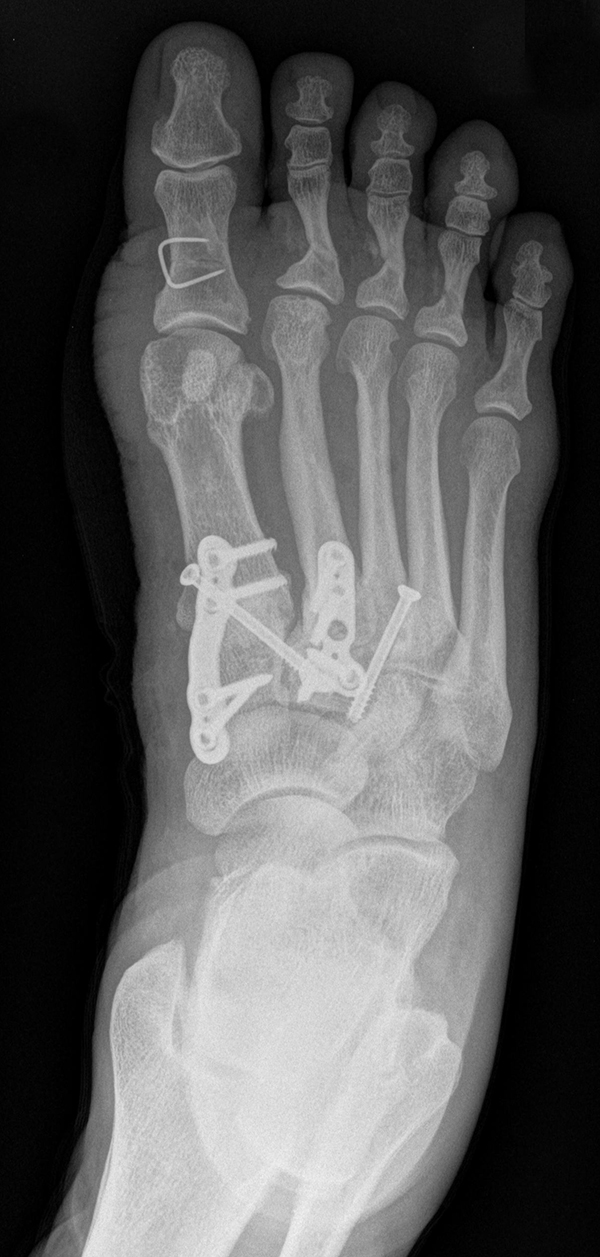

Die Korrektur des Spreizfußes und die Stabilisierung des TMT I ist das zentrale Element zur Entlastung des TMT II und III Gelenks. Dadurch kann die Lastachse wieder auf den ersten Strahl geführt werden. Aus Gründen der Stabilität sollte die Indikation zu einer Lapidusarthrodese großzügig gestellt werden. Eine TMT II und ggf. TMT III Arthrodese wird dann unter Berücksichtigung des Metatarsalindex unter Längenerhalt oder leichter Kürzung durchgeführt. Beim Pes metatarsus adductus kann der Eingriff mit einer Achskorrektur durchgeführt werden, um die Adduktionsstellung des Mittelfußes zu korrigieren (Abb. 9 und 10).

Zum Lesen der Bildbeschreibung und zur Vollansicht bitte die Bilder anklicken. Bilder: C. Hase

Es gibt neben der Möglichkeit mit der in situ TMT II, III Arthrodese auch die Möglichkeit Fehlstellungen wie den Pes metatarsus adductus zu adressieren (Abb. 9 und Abb. 24 zeigen das prä- und postoperative Röntgenbild eines Patienten mit Pes adductus Korrektur).

Zum Lesen der Bildbeschreibung und zur Vollansicht bitte die Bilder anklicken. Bilder: C. Hase.

• Röntgenkontrolle nach 8-10 Wochen, dann - je nach knöchernem Durchbau - Übergang zur Vollbelastung im Konfektionsschuh (Abb. 24 und 25).